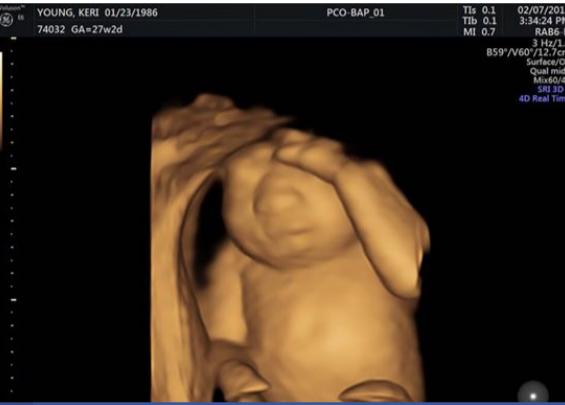

Američanka Keri Young je srečno poročena ženska in ponosna mamica 2-letnega Harrisona. Dolgo sta si z lahko močno želela drugega otroka. Po dolgih poskusih so končno ugotovili, da je Keri noseča. Srečna starša je izvedla, da pričakuje punčko. Vse je potekalo po načrtih. Dokler ni šla Keri v 20. tednu nosečnosti na ultrazvok.

Kot bi mignil, se je veselo pričakovanje spremenilo v grozo bodočih staršev. Zdravniki so pri plodu odkrili rdečo mutacijo, ki je dodatno pravilen razvoj možganov in lobanjskih kosti. Pričakovana življenjska doba otrok, rojenih s to napako, je le nekaj ur. Keri je bila postavljena pred grozljivo odločitev – izpeljati nosečnost do konca, saj je vedela, da bo rodila otroka, ki bo živel le nekaj ur, ali pa splaviti.